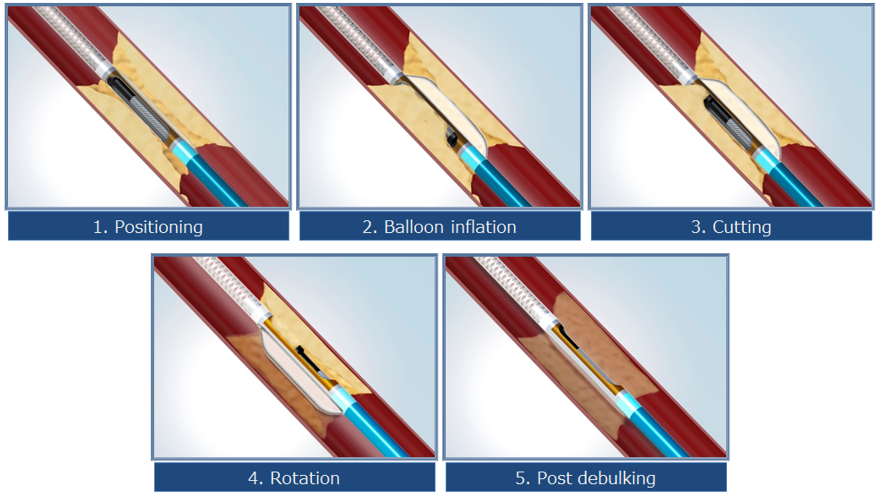

DCA(方向性冠動脈粥腫切除術)

冠動脈のプラークを切除し、体外に取り出します。プラーク量が減ることで狭窄が解除され、場合によってはステントを留置せずに治療を終えることもできます。

以下は当院で施行したDCAの症例です。赤矢印の部分に狭窄がありましたが、DCAで削り取ることで、ステントを留置することなく治療を終えました。術後数年経過しますが、再狭窄なく病状は安定しております。

症例紹介

症例患者様:60歳代 男性

症例治療内容:DCA(方向性冠動脈粥腫切除術)にてプラーク切除後に薬剤溶出性バルーンで拡張し良好に開大した。

症例治療回数:1回